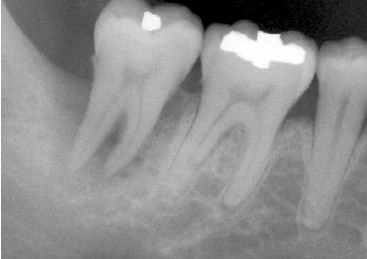

Hình 15. Khi răng có ống tuỷ rộng hơn so với răng cùng loại hoặc so với răng cạnh nó thì nên nghi ngờ có nứt dọc chân răng